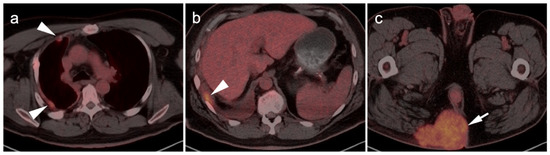

4.4. Bronchial Carcinoid

4.5. Pheochromocytoma and Paraganglioma